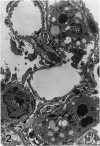

Abundant inflammatory cells such as polymorphonuclear leucocytes and macrophages accumulated and adhered to the endothelial surface of glomerular and intertubular veins and capillaries in rat kidneys after administration of bacterial lipopolysaccharide (LPS). There was also damage to both endothelial cells and proximal tubular cells, including intracytoplasmic oedema, and an increase in the number of lysosomes in the proximal tubular cells in the LPS-treated samples. Immunocytochemistry was used to demonstrate tumour necrosis factor (TNF) and leukotriene (LTR) in both LPS-treated and control samples. Immunoreactive LTR seen in the lysosomes of inflammatory cells attached to the endothelial cell surface may indicate the onset of endothelial cell damage. Positive immunoreactive TNF and LTR were seen on the endothelial cell surface only in the LPS-treated samples, indicating that TNF and LTR may enhance the adhesion of leucocytes to endothelium. Positive reactions of TNF and LTR in lysosomes of the mesangial cells suggest that lysosomes of such cells may be involved in the synthesis and storage of TNF and LTR. In addition to these reaction sites, lysosomes of proximal tubular cells were immunoreactive for LTR. These endogenous LTRs may be implicated in the degeneration of the proximal tubular cells.